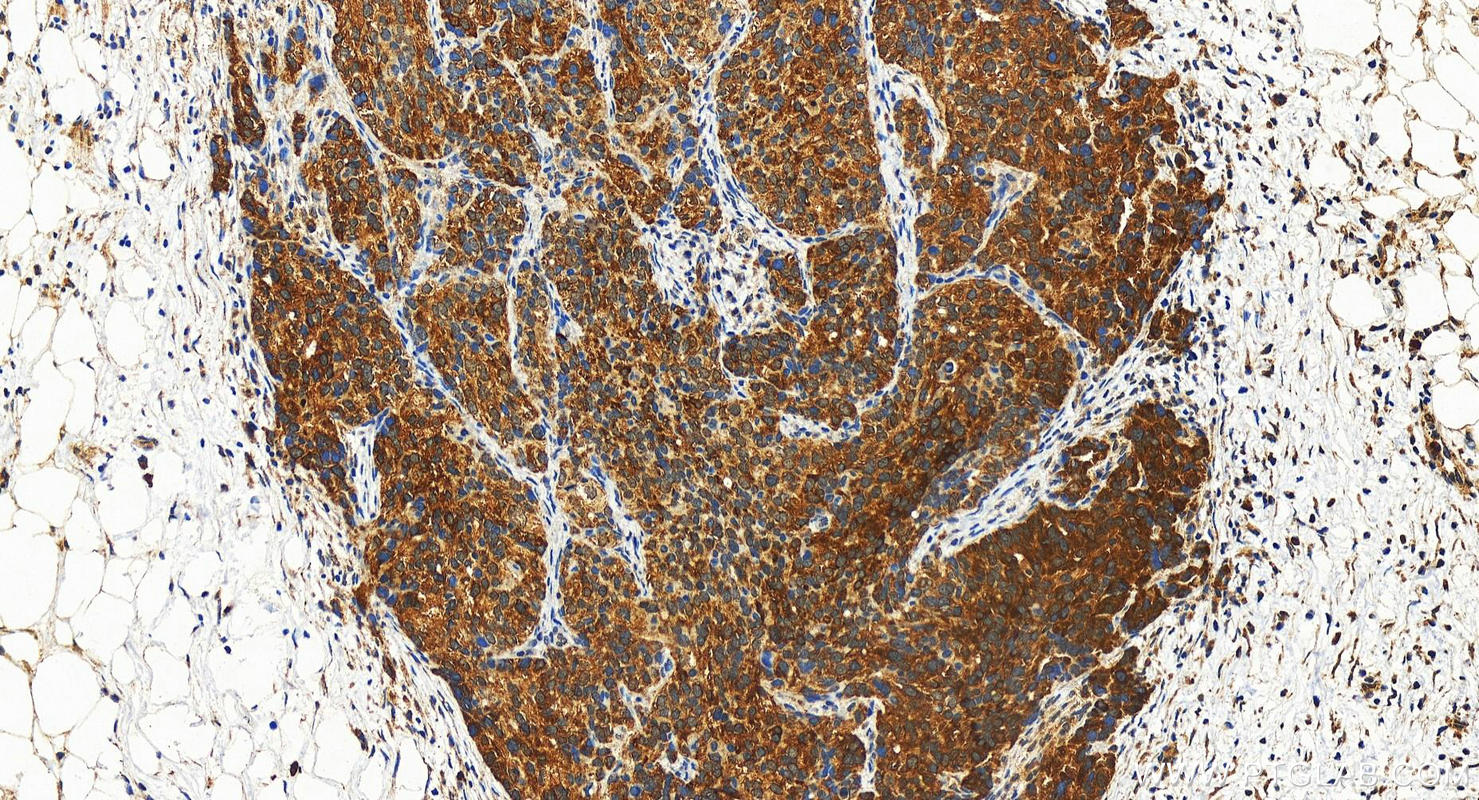

| Positive IHC detected in | human ovary cancer tissue, mouse cerebellum tissue, mouse pancreas tissue Note: suggested antigen retrieval with TE buffer pH 9.0; (*) Alternatively, antigen retrieval may be performed with citrate buffer pH 6.0 |

| Immunohistochemistry (IHC) | IHC : 1:50-1:500 |